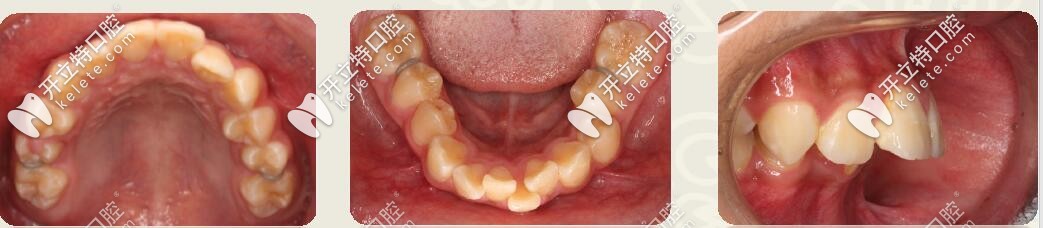

之前也看過很多地包天、偏頜、牙列擁擠等做牙齒矯正的真人分享~~今天,是一位13歲小孩偏頜+單側(cè)后牙反頜,用不對稱擴弓法+戴金屬托槽做矯正的實例,一起來看看效果怎么樣吧!